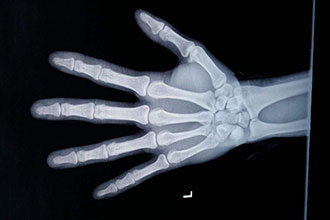

测骨龄能预测孩子身高吗?关于骨龄你需要知道这些科普中国-乐享健康 2019-01-07 作者:徐斌 |